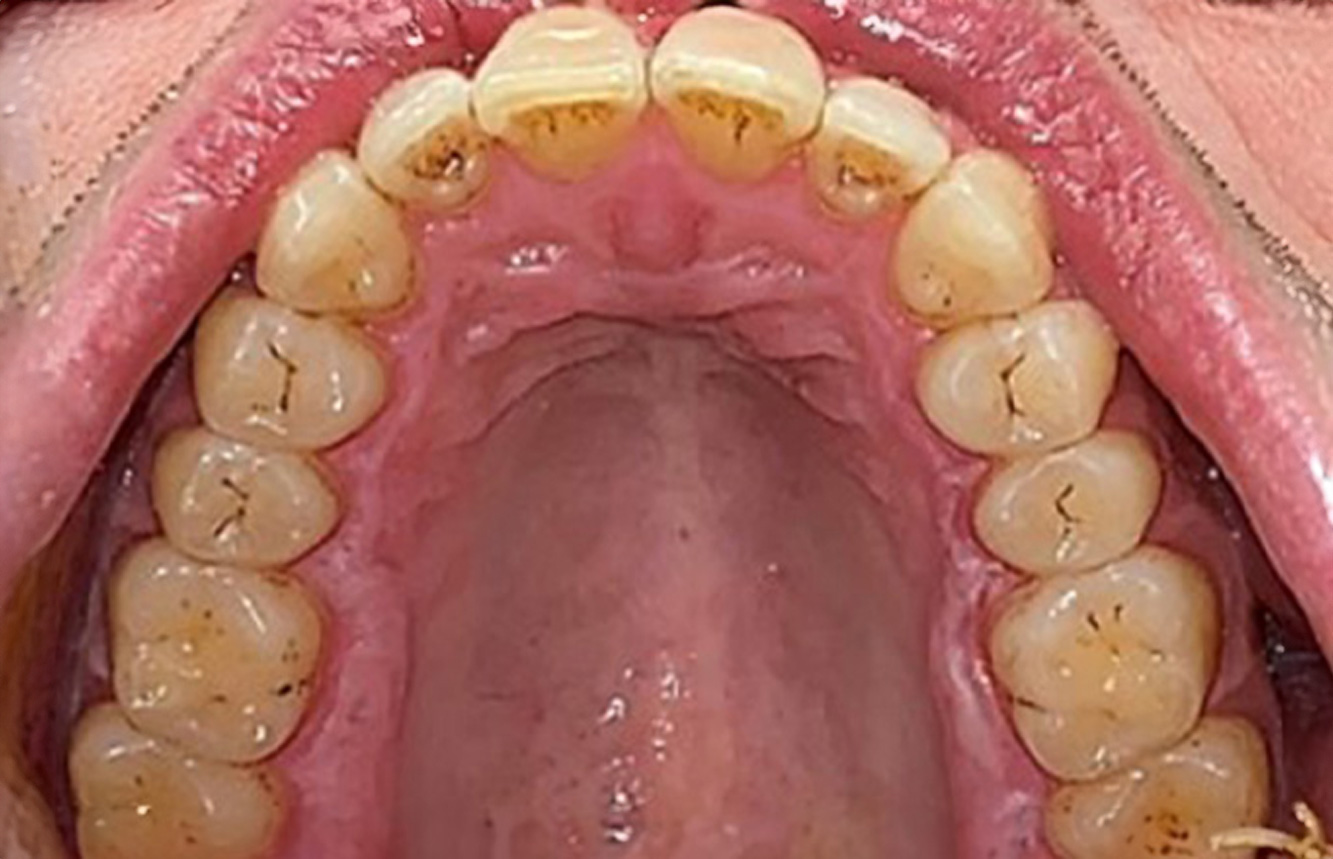

The (orally) healthy patient with implants

In the medical history, the 55-year-old patient states that he has no systemic disease and is not taking any medication. The patient’s lifestyle is similarly unremarkable. The patient has a few tooth restorations and two implants (2nd and 4th quadrants). On the basis of current findings, gingivitis is identified in an otherwise stable periodontal condition on the reduced periodontium (stage III, grade A). more